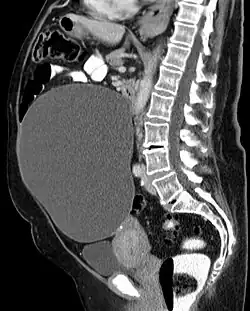

Muzinöses Zystadenom des Eierstocks: Computertomographie.